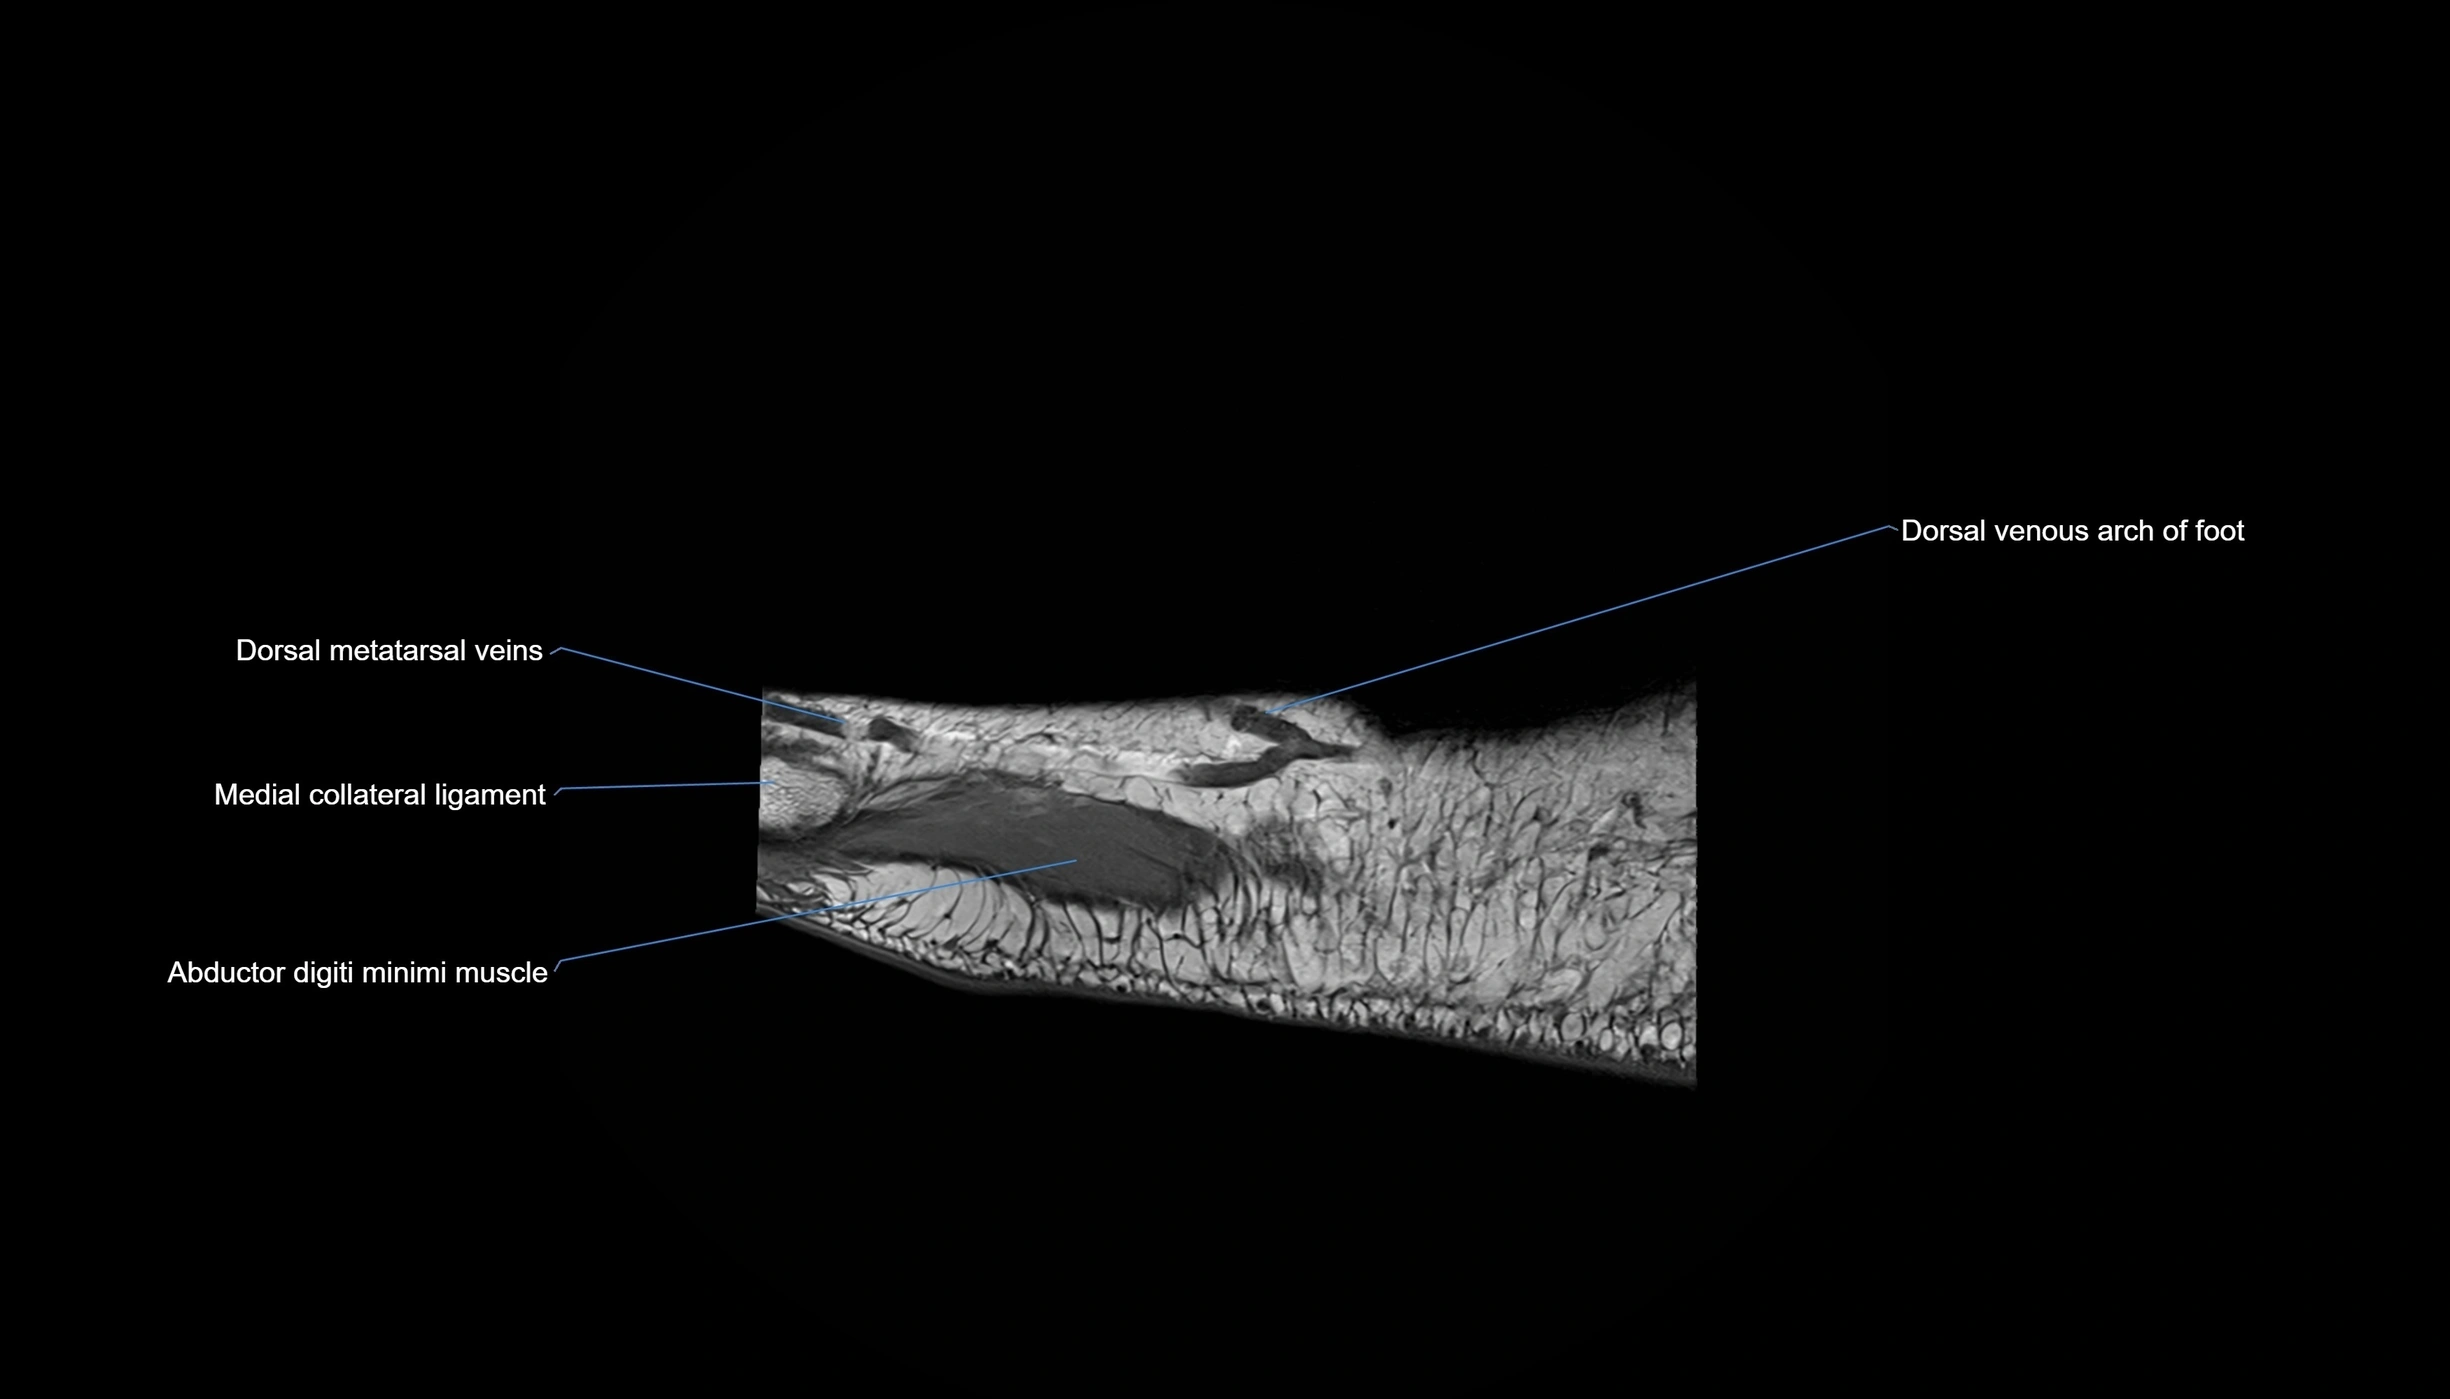

MRI image